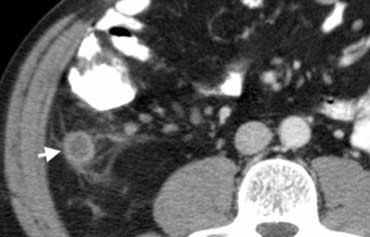

Hình 4. Nam giới 43 tuổi bị viêm ruột thừa. CT có tiêm thuốc cản quang cho thấy ruột thừa giãn chứa dịch (mũi tên) với thâm nhiễm mỡ quanh ruột thừa.

Trên CT, ruột thừa viêm được bao quanh bởi dấu hiệu thâm nhiễm mỡ (Hình 4).